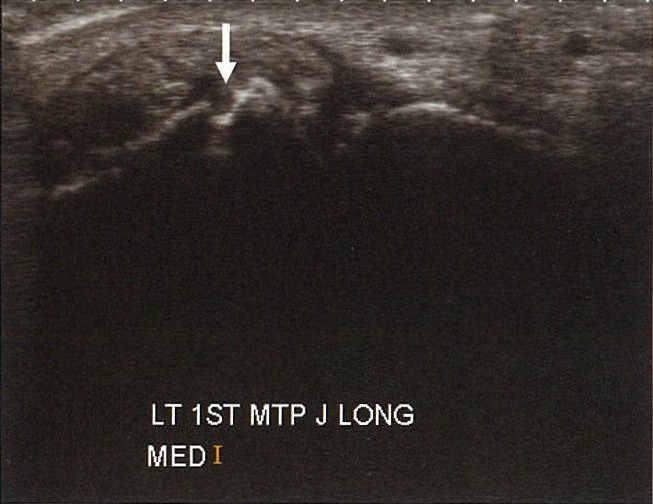

近年來,骨骼肌肉超音波應用在類風濕性關節炎病人的主要適應症,包括偵測無症狀的關節滑囊發炎(圖1)、傳統X光檢查無法偵測的關節骨頭侵蝕(圖2)、評估肌腱病理變化(圖3),以及在超音波導引下進行關節與軟組織的液體抽取與關節腔內藥物注射(圖4)。

圖1

痛風是一種常見的關節炎,主要肇因於高尿酸血症,因尿酸結晶沈積在關節的滑囊或軟骨上而造成急性或慢性的關節炎。依骨骼肌肉超音波觀察所見,急性關節炎常會造成大量關節積液,同時在積液中有細胞殘渣形成如雪花般的蛋白懸浮液(圖6)。最典型的尿酸沈積型態為在關節軟骨表面的線狀沉積,由於是形成連續線狀構造,故稱為雙輪廓徵象(圖7)。長期痛風石的沈積常會形成非均質性的陰影甚至形成鈣化(圖8)。同時,痛風所造成的骨頭侵蝕也不少見(圖9)。